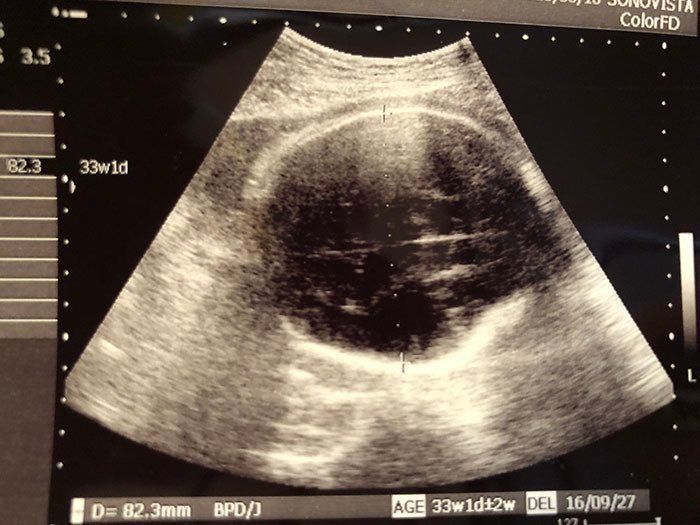

妊娠34週目 予定日が近づき、気持ちが落ち着かない日々

妊娠34週目の健診日。仕事を辞めたせいか、幸いにも血圧は平常値に。安静を心がけ外出は控えましたが、運動不足の解消を兼ねて、ベビーベッドの組み立てやベビーアイテムの収納作りをして過ごしていました。